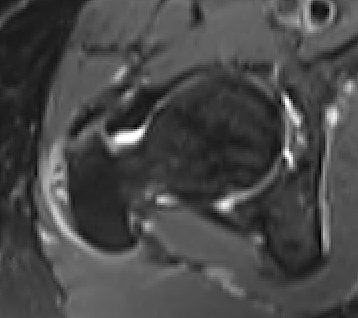

Intact gluteus medius insertion

Torn gluteus medius and minimus

Acute tear gluteus medius